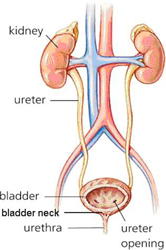

The kidneys alone perform the functions just described and manufacture urine in the process while the other organs of the urinary system provide temporary storage reservoirs for urine or serve as transportation channels to carry it from one body region to another. The article anatomy and physiology of the kidney is the basis for this aorn journal independent study.

The kidneys are 11 centimeters long paired reddish brown organs situated on the posterior wall of the abdominal cavity one on each side of the vertebral column and capped by the adrenal gland. H ions are produced as a natural byproduct of the metabolism of dietary proteins and accumulate in the blood over time. Connective tissue anchors the kidneys to surrounding structures and helps maintain their normal position.

Due to the presence of the liver the right kidney is slightly lower than the left kidney. They are about 1114 cm in length 6 cm wide and 4 cm thick and are directly covered by a fibrous capsule composed of dense. Anatomy of the urinary system.